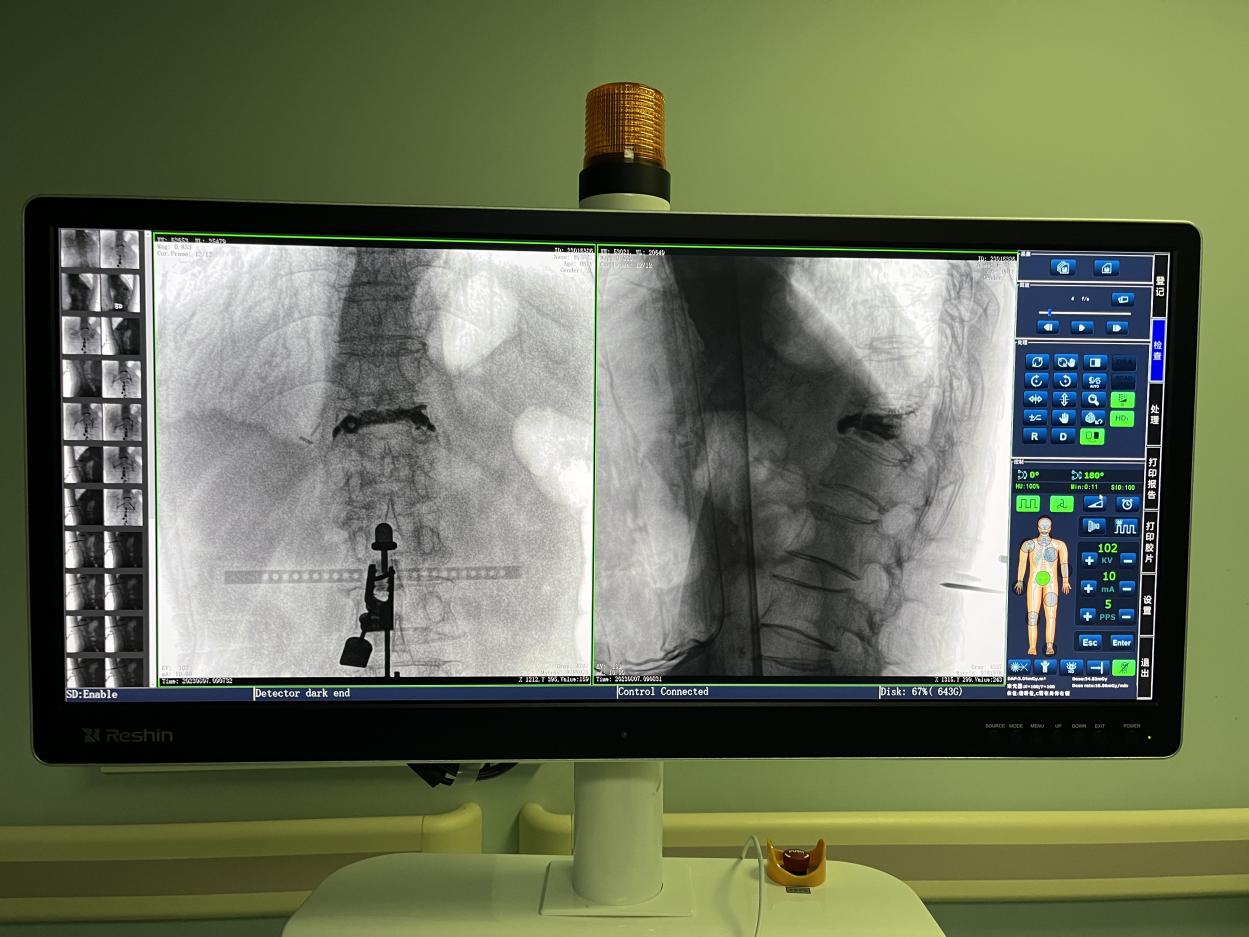

PL300B搭配普爱医疗自主研发生产的平板三维C形臂使用,通过三维立体术中图像,手术医生可从各个方位观察合适的手术入路,并进行关键数据测量,从而最大限度地避开危险区。

骨科机器人手术-术中影像